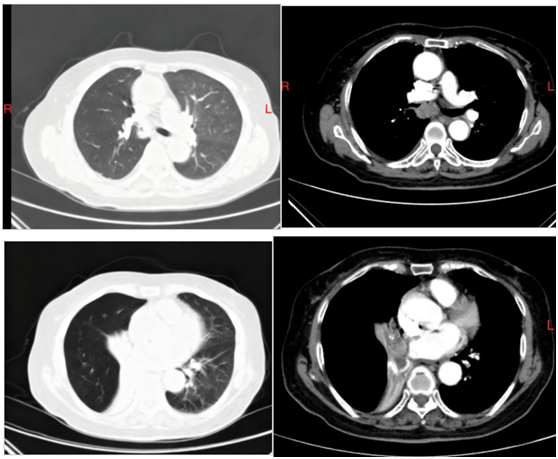

夏奶奶近两年来一直被间断的胸闷、气短、咳嗽、咳痰困扰。半月前,她的病情急剧加重,出现了痰中带血的症状,家人紧急送至东院区。呼吸与危重症医学科阎杰副主任医师接诊后,立即为夏奶奶进行胸部增强CT检查。结果提示“右肺门增大,右肺主支气管内结节状软组织密度灶,右肺下叶不张”,高度怀疑恶性肿瘤。

收治入院后,李小忠主治医师迅速评估病情,并与家属充分沟通。为明确诊断并解除气道梗阻,决定为夏奶奶进行电子支气管镜检查。术中发现,夏奶奶的右主支气管已被新生物完全堵塞,内镜无法通过。

面对挑战,尚东主任果断决策,先后运用电圈套、氩气刀介入技术进行治疗,清除了部分肿瘤,右肺上叶暴露。术后,夏奶奶的气短症状得到明显改善。然而,由于肿瘤(后经病理证实为“腺样囊性癌”)根基宽、浸润生长特性强,右中间支气管仍未被完全打通,右肺下叶持续不张。

术后3天,复查气管镜,原本狭窄的管腔已显著好转,右肺下叶及右中叶支气管开口清晰可见,夏奶奶的呼吸变得顺畅,气短症状极大缓解,未再出现咯血,目前已顺利出院。